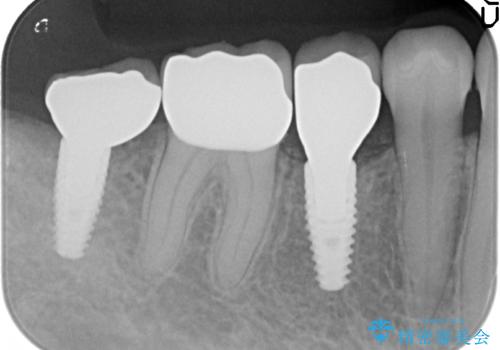

- 右下の奥歯の被せ物が外れてしまったので診て欲しいといらっしゃった方の症例です。

右下7は欠損しており、右下5は保存不可能だったため、インプラントによる欠損補綴を行いました。

インプラント埋入時には骨が不十分な部位に骨増生を行っております。

当院では主にストローマンという種類のインプラントを治療に用いています。

ストローマンは世界的にもNo1のシェアを誇り、骨との適合にも優れたインプラントです。